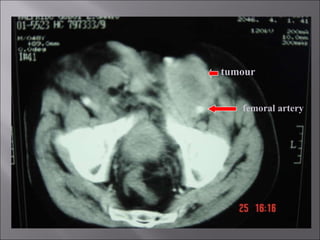

T3 lesion

total penectomy

femoral artery tumour